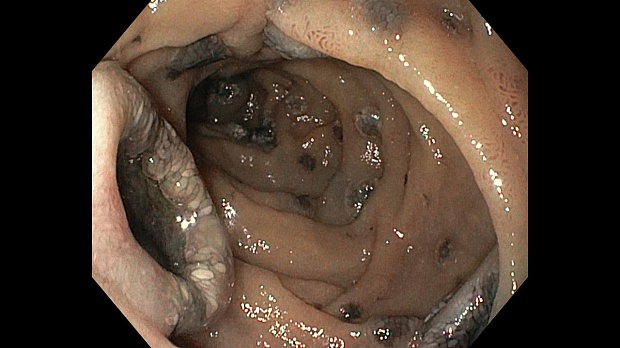

меланома ДПК.jpeg)

меланома ДПК.jpeg)

меланома ДПК.jpeg)

меланома ДПК.jpeg)

Эзофагогастродуоденоскопия диагностическая

12-кишка: Просвет луковицы двенадцатиперстной кишки обычный, содержит небольшое количество желчи, перистальтика активная , слизистая оболочка розового цвета, ворсинки сохранены. Так же прослеживаются пигментированные образования от 2мм до 8мм. серо-синюшного оттенка. Постбульбарном отделе множественные пигментые образования до 10мм, единичные кратообразные пигментные образования до 15мм, глубиной до 5мм., дно покрыто серым фибрином. Биопсия 2-а кусочка.

Заключение: ГПОД. Грыжевая гастропатия. Эрозивная гастропатия антрального отдела желудка. MTS Меланома ЛДПК, залуковичного отдела. Биопсия.